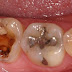

Berbagai penyebab yang lain dari sakit gigi ialah karena gigi yang berlubang, seringkali hal ini terjadi pada remaja ataupun anak kecil yang masih menyukai makanan dan minuman sembarangan yang berakibat merusak pada gigi.

Efek yang ditimbulkan oleh si penderita tidak seketika itu ketika dia memakan dan meminum makanan yang menyebabkan gigi rusak, namun dengan berjalannya waktu dan kebiasaan yang kurang baik tetap dilakukan maka lama-kelamaan akan muncul gejala gigi rusak. Efek dari Sakit gigi ini diantaranya dapat menjadikan si penderita tidak dapat tidur dengan nyenyak dan juga kepala pusing, mudah marah akibat suasana sekitar yang gaduh, dan tidak bisa memusatkan perhatian pada satu titk. Selain itu banyak juga kasus sakit gigi ini disebabkan oleh kerusakan gigi, bisa karena retak, kropos atau penyakit gusi.

Namun penyebab sakit gigi yang sering terjadi adalah karena terdapatnya bakteri pada gigi yang sedikit-demi sedikit menjadikan gigi berlubang. Tapi dalam beberapa kasus sakit gigi tidak hanya karena gigi yang bermasalah, tapi bisa juga dikarenakan gusi yang terinfeksi atau mengalami pembengkakan.